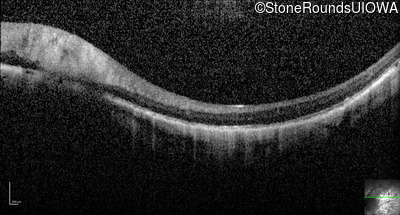

Optical Coherence Tomography - Left - 5/200

Exemplar / OCT Stack